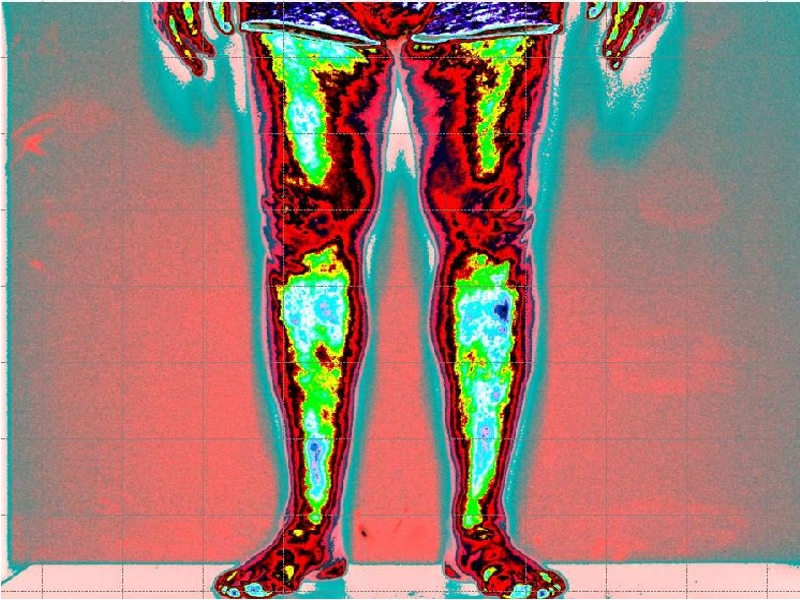

Dopo il trattamento con Renovatio, riduzione netta della tensione muscolare globale (colore azzurro, normalità di tensione)

Sintomatologia riduzione del dolore e maggior flessibilità del tronco.

Leggenda: colore rosso inattivazione tensione muscolare

Verde, minima tensione muscolare

Azzurro normale tensione muscolare

Blu scuro, aumento della tensione muscolare